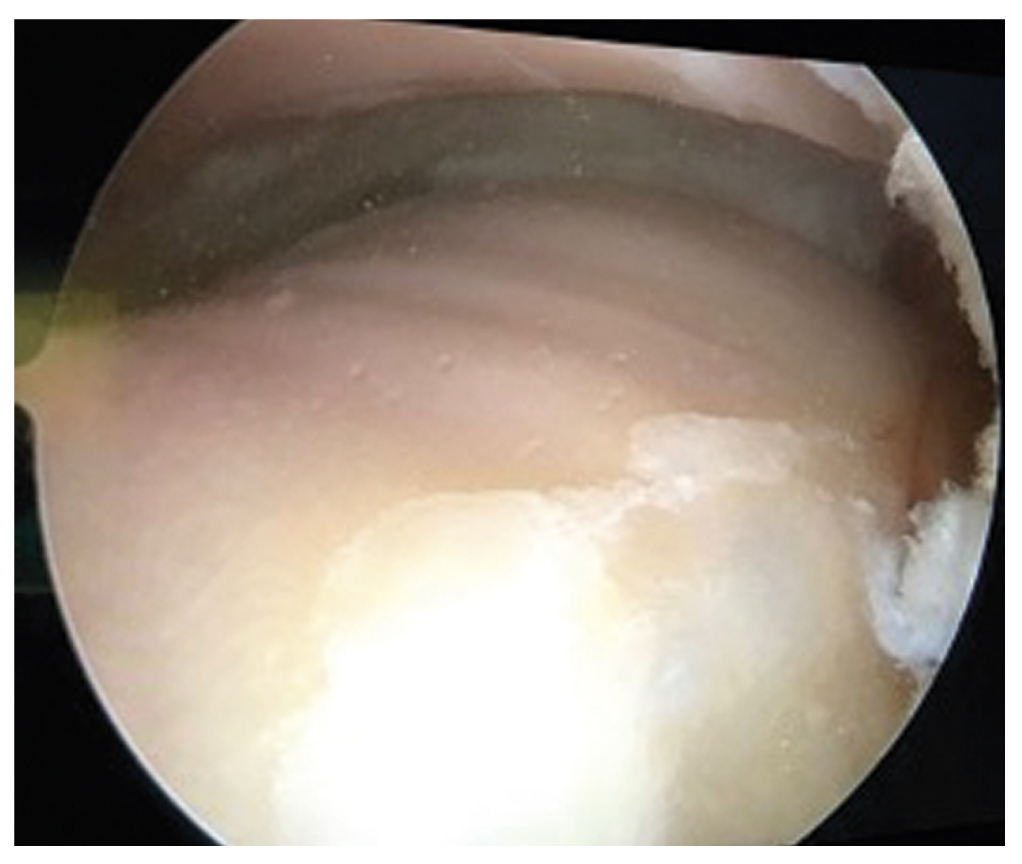

Patient No. 1 before the distraction arthroplasty of the ankle joint had a total absence of cartilage tissue (grade IV according to the Outerbridge scale) (Fig. 3). At the moment of de-installing the Ilizarov frame, repeated arthroscopy was carried out, revealing the presence of abundantly vascularized soft connective tissue, which was completely filling the ankle joint cavity. The arthroscopic signs of arthrofibrosis are provided in Fig. 4.

Fig. 3. Total absence of cartilage tissue of the talus of patient No. 1 before ankle distraction arthroplasty.